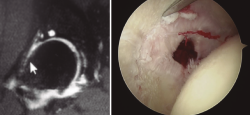

Un gesto añadido que podemos hacer, sin conocer exactamente la repercusión clínica del mismo, es la retirada del osteofito central con fresas o material cortante curvo (Figura 4).

Figura 4. Paciente con osteofito central acetabular (imagen izquierda). Resección del osteofito central (imagen derecha).